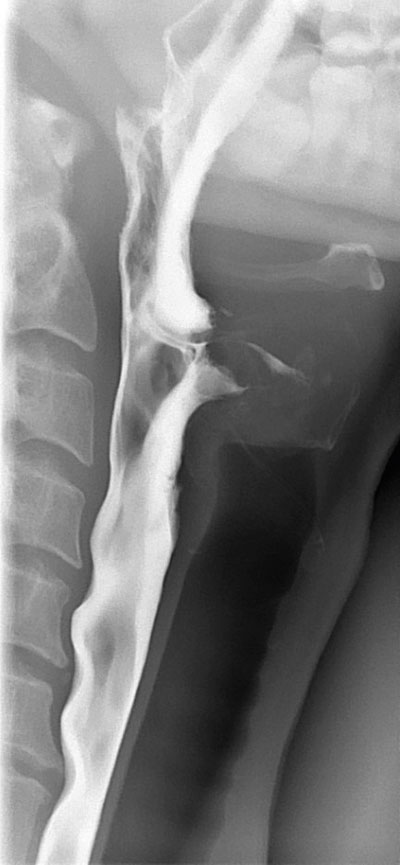

Bild från sväljningsröntgen i sidoprojektion. På bilden ses osteofyter på ryggkotorna som ger avtryck på matstrupen. Matstrupen är fylld med kontrast, detta är en ögonblicksbild. Osteofyterna hos denna patient ger inte dysfagi.